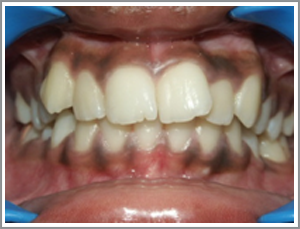

Case 3

Before

After

MNL a 14 year old girl presented with the protrusion of her front teeth. (Angles class I bimaxillary proclination).

Problem list : not able to close lips due to the excessive tooth projection. Lips looking too protrusive when they were closed.

Treatment plan : extraction case – case was treated with the extraction of four first premolars. The front teeth (incisors and canines) were then taken back and the patient had a pleasing appearance and could close her lips.

Treatment time : 20 months